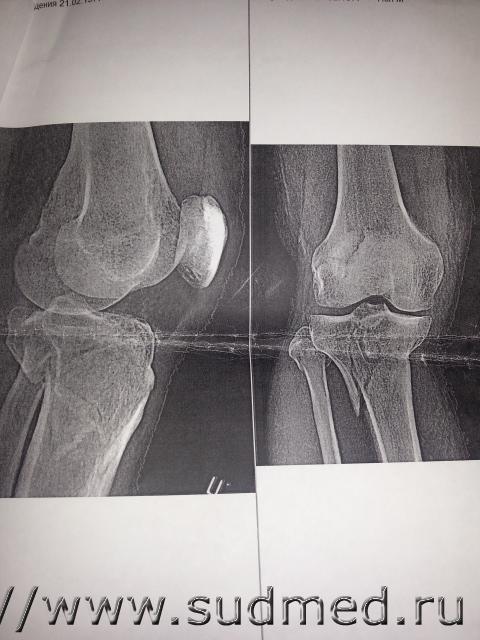

вот другое изображение.Судебная медицина - Прикрепленное изображение

Перелом захватывает диафиз.

А есть всетаки перелом диафиза большеберцовой кости и какой вред здоровью тут будет - средний или тяжкий и каким пунктом Правил определения степени тяжести вреда здоровью надо руководствоваться.

Пункт 6.11.8.

Тяжкий вред.